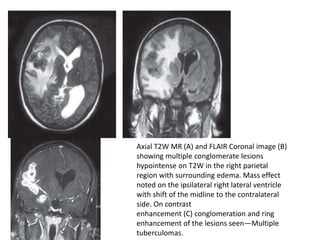

Axial T2W MR (A) and FLAIR Coronal image (B)

showing multiple conglomerate lesions

hypointense on T2W in the right parietal

region with surrounding edema. Mass effect

noted on the ipsilateral right lateral ventricle

with shift of the midline to the contralateral

side. On contrast

enhancement (C) conglomeration and ring

enhancement of the lesions seen—Multiple

tuberculomas.